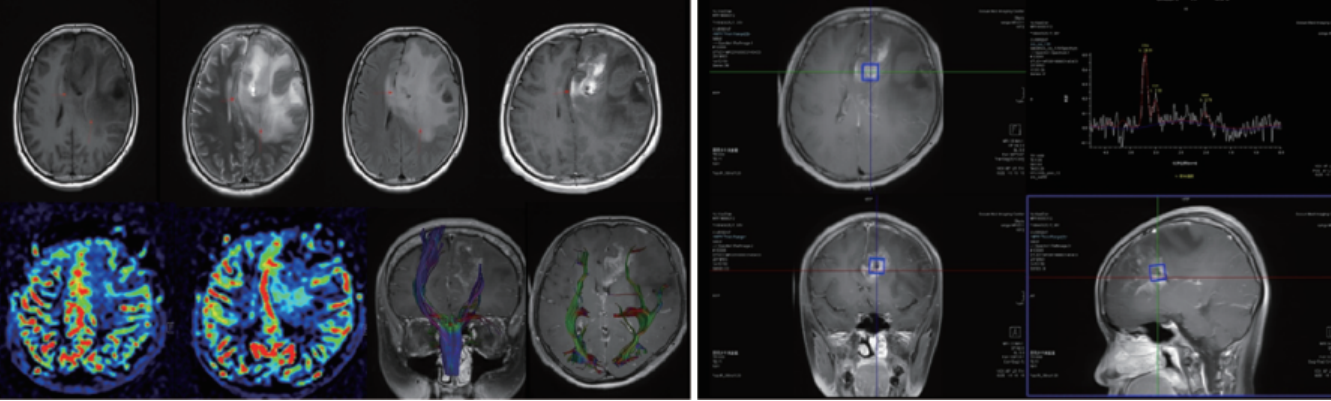

腦腫瘤波譜、灌注、DTI